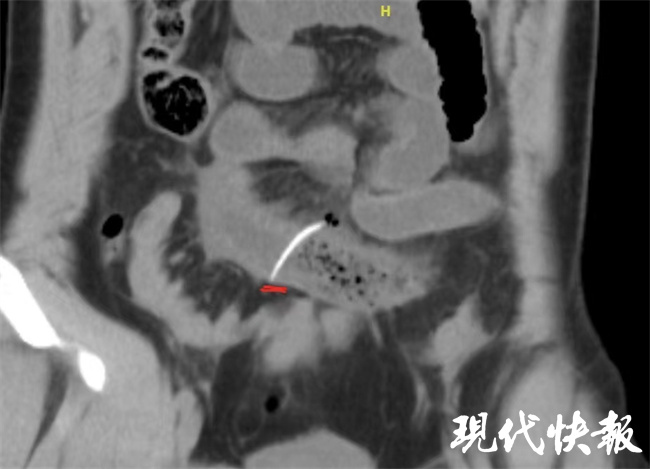

普外科是专门处理急腹症的首要会诊科室,王长林主任医师会诊再仔细阅片时发现肠管内见高密度影,尖锐细长,像是鱼刺,再次追问小张有没有吃鱼,小张这才恍然大悟,自己两天前确实吃过鱼,但是吃饭过程中并没有感觉卡到鱼刺,吃完后也没觉得不舒服。

难道真的是因为鱼刺?王长林表示,像小张这种情况,CT显示有游离气体代表有消化道穿孔,位置在小肠,原因大概率是鱼刺。这让他想起来上周一个病人吃大枣出现穿孔的,两个人表现一模一样,因腹痛来的,检查腹部CT提示游离气体,看到高密度影,取出来之后才发现是大枣核,一端特别尖锐,刺破肠管。不小心吃了异物,大部分人都有机会正常排走,但有一部分病人,像小张这样的,异物太尖锐,已经刺破小肠管了,就需要手术了。

在经过相关准备后,王长林主任医师、于一龙医师为小张进行了手术。小肠的长度一般在4米到6米左右,在腹腔内弯曲堆叠在一起,鱼刺很难确定在小肠的哪一段,手术过程中需要仔细查找。更难的是,这么细的鱼刺,还会在小肠内运动,2天过去了很有可能游离到其他地方,在穿孔附近不一定能够找到鱼刺。而且穿孔位置不是一个孔,是一片小肠漏气,修补存在肠瘘风险,果不其然,经过仔细探找,在距离穿孔位置大概20cm的地方找到了鱼刺,在安全的情况下,将鱼刺送回到穿孔的位置,成功取出,并完成小肠的部分切除吻合手术,避免急性期修补导致的肠瘘。